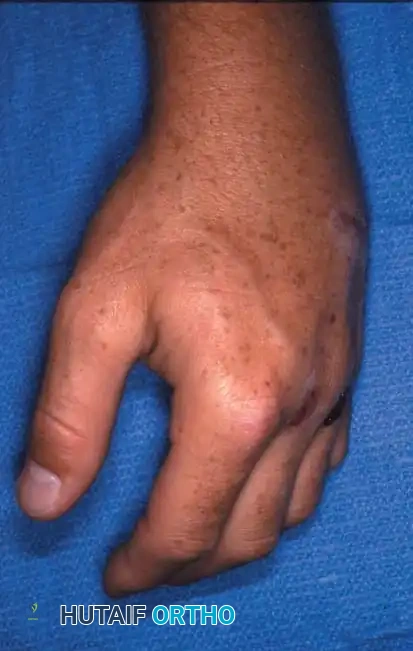

Fig. 64-31 Dislocation of fourth and fi fth carpometacarpal joints. A, Clinical appearance of hand before reduction. Note dorsoulnar hand swelling consistent with injury. B, Posteroanterior view. C, Lateral view. D, Oblique view. E and F, Traction was adequate to reduce, and splint was satisfactory to maintain reductions.